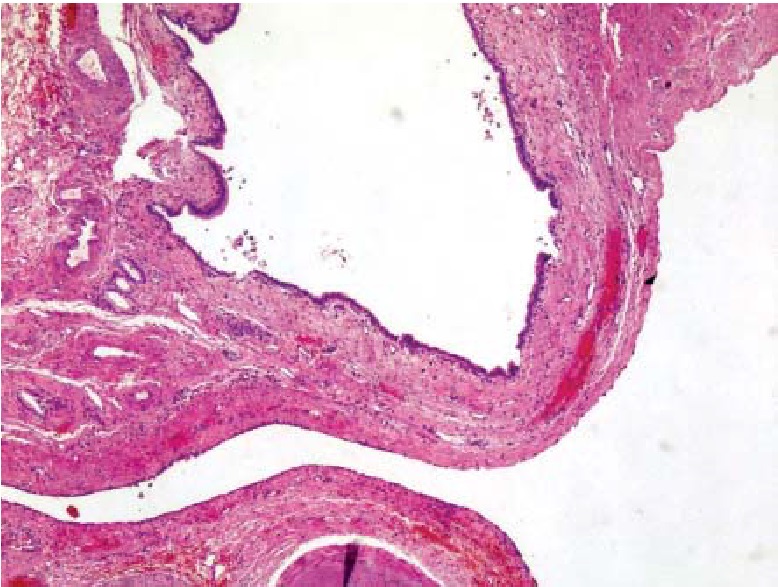

Рис. 4. Гистологическое строение стенки кисты. Окраска гематоксилином и эозином, ув. ×40

По результатам патогистологического исследования фрагментов стенки кисты выявлена фиброзная стенка кисты с преимущественно уплощенной выстилкой, местами выстилка аналогична выстилке желчных протоков, а также солитарная киста желчного протока. По периферии обнаружены единичные кистозно-расширенные желчные протоки, небольшие фрагменты ткани печени с очагами гемосидероза.